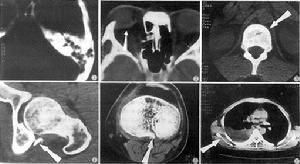

故凡頭顱外傷後有聽力損失、鼓膜破裂或鼓室積血、或有眩暈、或有面癱者皆為中耳及內耳受損所致,即可診斷顳骨骨折,X線攝片可顯示骨折線。橫行骨折較易顯示,X線未發現骨折時,仍不能排除顳骨骨折。

診斷檢查

病情許可時,可行顱底營影像學檢查。預後縱行骨折引起的傳導性聾多可經鼓室車形術或窗膜修補術等得到恢復。橫向骨折導致的感音性聾常難改善,前庭功能喪失者可以逐漸代償。頭顱外傷癒合或,骨折縫隙仍可存在,日後中耳感染時,有引起腦膜炎的可能,橫行骨折較縱行骨折的預後要吃,兒童患者的預後較成人為佳。

3、傷情未全面了解者,待全身情況穩定或好轉後,應作顱底X線拍片及CT掃描、神經檢查和耳科檢查,如後遺鼓膜穿孔、聽骨斷離,傳導性聾或面神經麻痹等症征及可於後期行鼓室成形術或面神經手術。